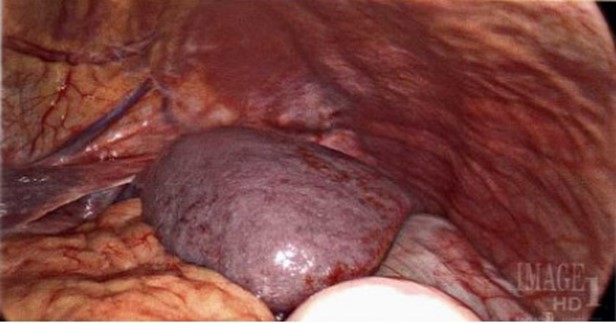

Figure 5: Intraoperative images of laparoscopic splenectomy for management of splenic torsion.

Upon creating a pneumoperitoneum and 12 mm umbilical optical port entry, an enlarged spleen was intraoperatively visualized to be enlarged, rotated with hilum facing laterally, and notably without supporting suspensory ligaments such as splenocolic, splenorenal, or gastrosplenic.